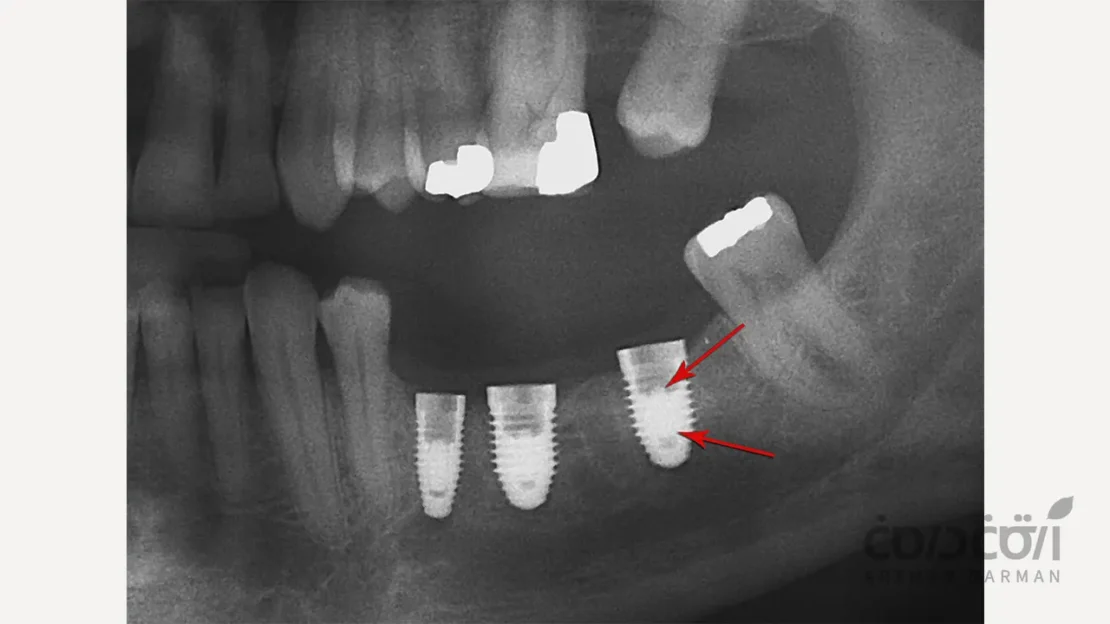

در یک شکستگی ایمپلنت دندان واقعی، خود پایه تیتانیومی که به طور کامل به استخوان جوش خورده است، دچار ترک یا شکست کامل می شود. این شکستگی معمولاً در ضعیف ترین نقطه ایمپلنت، یعنی در ناحیه گردن آن (نزدیک به محل اتصال به اباتمنت) رخ می دهد.

- تهیه رادیوگرافی (X-ray): این مهم ترین ابزار تشخیصی است. در رادیوگرافی، یک خط شکست واضح در بدنه ایمپلنت قابل مشاهده است. گاهی برای بررسی دقیق تر، از اسکن سه بعدی (CBCT) استفاده می شود.